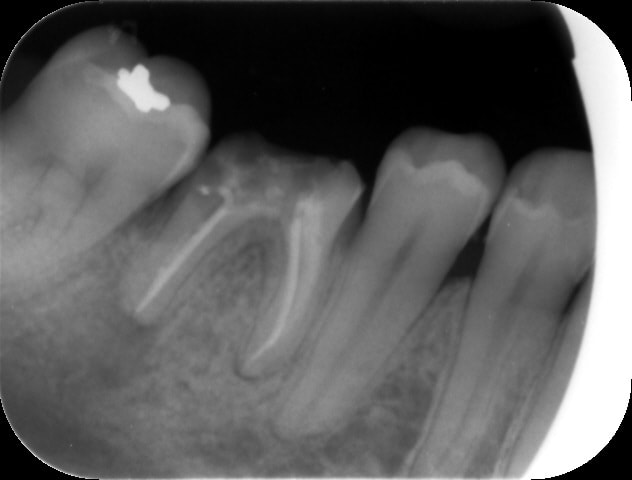

Regardez là j'ai fait faire un scanner en sachant à l'avance que ça ne servirait à rien ...

Résultat : irradiation inutile, supplément pour la patiente etc etc

Et des comme ça on en a tous régulièrement

Tu n'as pas loin d'avoir raison. Mais comment par un simple examen clinique es tu sûr de ne pas avoir une ostéïte chronique? J'en ai eu qu'une seule en 30 ans certes mais j'ai été bien content que mon radiologue me stoppe. Tu imagines si j'avais planté? C'était total asymptomatique!